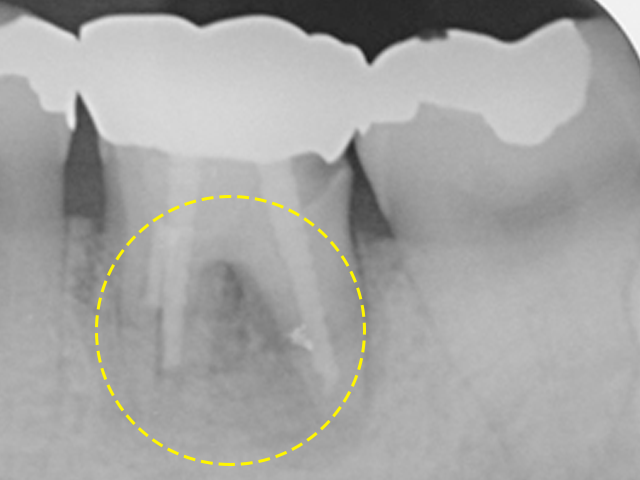

최창수치과에서는 최대한 본인 치아를 살릴 수 있도록 치주치료 및 골이식

등의 방법을 이용하여 주기적인 관리를 도와드리고 있습니다.

자연치아살리기를 실천하고 있는 최창수치과에서는 소중한 자연치를 살리고 보존하는 다양한 방법들을 보유하고 있습니다. 환자분들의 현재 구강 상태에 대해 세심하게 진료하여 파악함으로써 불필요한 발치가 진행되지 않도록 체계적인 시스템 아래 솔루션을 제공하고 있습니다.

자연치아 치료 과정